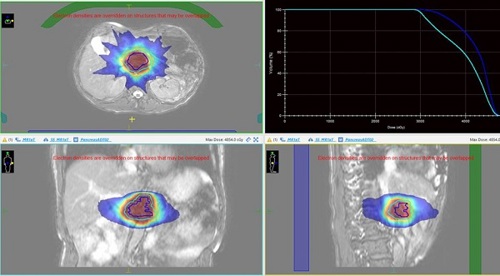

Below is a picture of a treatment plan for a patient with a pancreas tumour. Note the high dose region in the red colourwash, covering the target (plus a margin for breathing motion) in the blue and cyan lines.